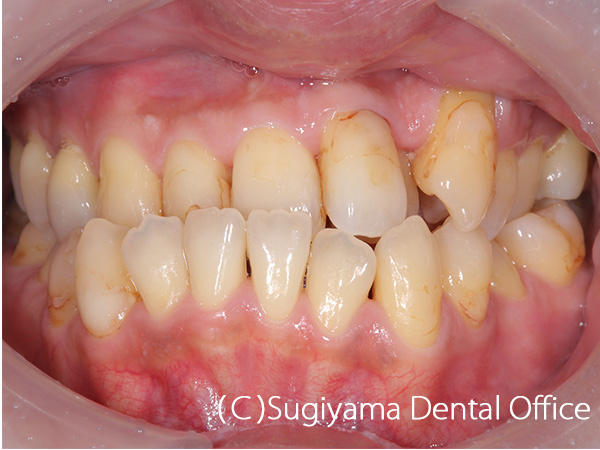

前歯を綺麗にしてほしいということで来院した女性の患者さんです。

親知らずは抜歯しましたが、そのほかは1本も歯を抜かずに矯正治療を仕上げました。

変色が著しかった前歯2本はオールセラミッククラウンで治しました。

歯が綺麗になったことで、笑顔がさらに美しくなりました。